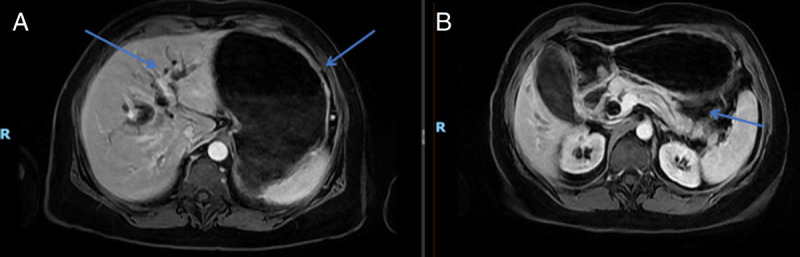

Double EUS-guided bypass for gastric outlet and biliary tract malignant obstruction: A standardized one-step approach (with videos).